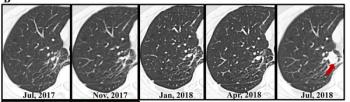

Researchers found comparable 10-year overall survival rates for people who had computed tomography (CT) surveillance (94.7 percent) and those who had surgery for ground-glass nodules (97.6 percent), according to a new prospective study involving over 680 participants.